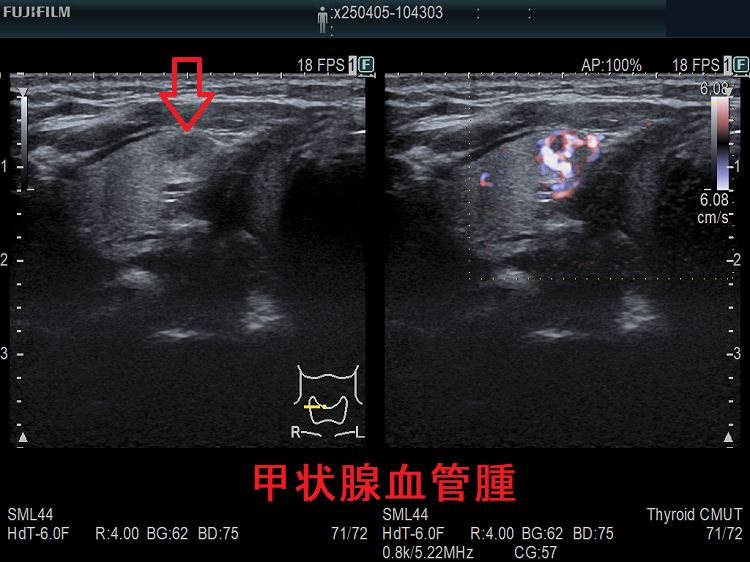

甲状腺に発生する血管腫は非常に稀で、日本の報告例もわずかです(日臨外会誌 72(3),579―583,2011)。

ケース①

ケース②

ケース③

甲状腺血管腫(拡大) ドプラーモード(eFlow);腫瘍内血管が3次元的に見え、毛玉の様。